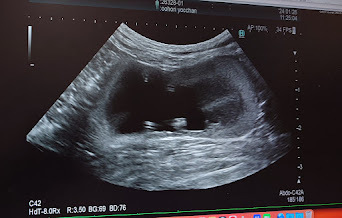

🐈エコー検査をしてもらい、腎臓と腎盂は相変わらず肥大したままでした。🐈

ヨッちゃんが腎盂が小さくならずに腎臓と腎盂が肥大したままとなっている要因で考えられるのが、ヨッちゃんの尿管が手術をしたので短くなっているんだけど、本来は拡張した尿管は術後に徐々に元の細さに戻っていくんだけど、ヨッちゃんは手術後にカテーテルを入れていた時の太さと現在の尿管の太さに変化がないままだったということが考えられる。もしかしたら尿管が太いままなので、膀胱と腎盂の陰圧が一緒になっており、うまく膀胱に流れていなかったり、膀胱から腎臓に逆流してしまってるのかもしれない。と先生から説明を受けました。

先生にネットを見ていたら水腎症という症状があって、ヨッちゃんの治療法や手術の方式と似ていたんだけど、ヨッちゃんは水腎症なんですか?と質問したら、水腎症も腎臓と腎盂が肥大するからヨッちゃんの症状や水腎症になる原因も尿管の詰まりからそうなることが多いからとても似ているんだけど、水腎症はもう皮1枚のところまでパンパンに肥大した状態のことを言うので、ヨッちゃんは腎臓腎盂は肥大しているけどそこまでいってないのと、水腎症はあくまでも症状の呼び方であって病名ではないんですよということを教えてもらいました。

ヨッちゃんが腎臓と腎盂が肥大していることから、逆流の可能性があるかもしれないということで、CT検査で造影剤を入れて逆流していないかを確認させてくださいという話になりました。CT検査は全身麻酔をするので検査前日の夜22:00から絶食と当日の朝7:00から絶飲しないといけないので、後日またCT検査で詳しく見てもらうことになりました。